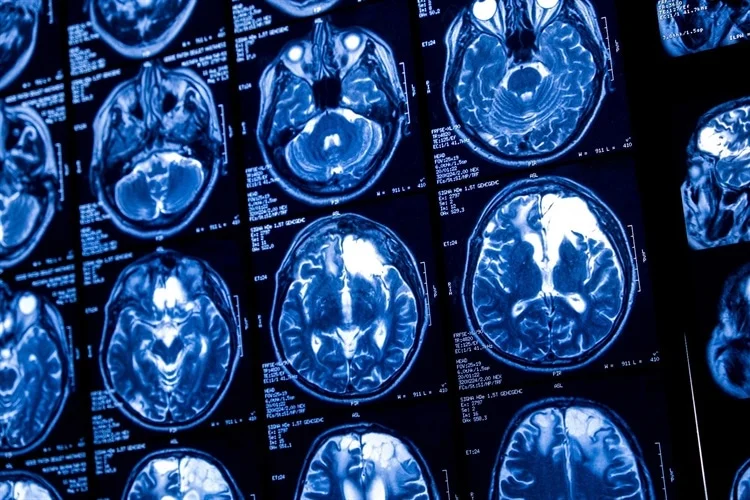

Brain tumors pose a significant health challenge, requiring precise and timely diagnosis to improve treatment outcomes. This study presents a deep learning-based approach for non-invasive brain tumor detection and classification using MRI data. By leveraging Convolutional Neural Networks (CNNs) and transfer learning models such as VGG16, Inception V3, and EfficientNet B2, the method effectively analyzes tumor features like texture, location, and shape. Using the Kaggle Brain Tumor Classification MRI dataset, the proposed model achieved superior accuracy compared to existing techniques, enhancing diagnostic efficiency while minimizing reliance on invasive procedures. This approach supports radiologists by improving diagnostic precision and streamlining clinical decision-making, contributing to reduced brain tumor-related mortality and better patient outcomes.

The brain, a highly complex organ with approximately 100 billion neurons and 1,000 trillion synapses, is prone to life-threatening conditions like brain tumors, caused by abnormal cell growth. In India, 28,000 cases of brain tumors are reported annually, with an alarming 86% mortality rate. Similarly, the United States anticipates 18,990 deaths from brain and CNS tumors in 2023. Brain tumors can be benign or malignant, originating either as primary tumors in the brain or secondary tumors spread from other organs. Common types include meningiomas, gliomas, and pituitary tumors, each posing severe risks due to increased intracranial pressure.

We used the publicly available Brain Tumor Detection and Classification MRI image Kaggle dataset are (https://www.kaggle.com/datasets/sartajbhuvaji/brain-tumor-classification-mri). There are 3264 brain MRI images in dataset which have been labelled as glioma tumor, meningioma tumor, no tumor and pituitary tumor. Including the number of these brain MRI images are 926 images of glioma, 937 images of meningioma, 500 images of no tumor and 901 images of pituitary tumor. The images were processed, they were divided into a training and validation set using an 80%-20% split respectively. Depending on their types and grades, brain tumor can vary in terms of size, location and shape.